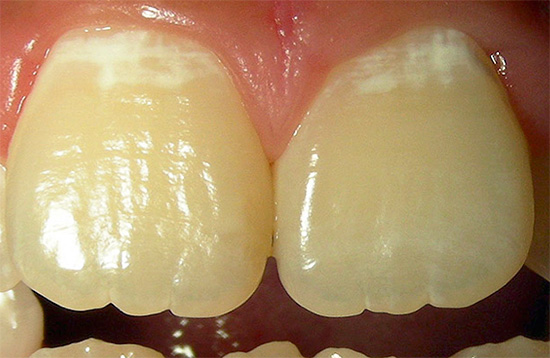

La carie viene mostrata nella prima fase di sviluppo quando si tratta di un punto bianco o gessoso (ecco come appaiono le aree dello smalto demineralizzato):

Questo stadio di sviluppo della patologia è chiamato stadio del punto bianco: qui si verifica solo il danno iniziale allo smalto e la formazione di pori in esso sotto l'influenza di acidi aggressivi dalla cavità orale. Lo smalto perde la sua lucentezza, acquisisce un colore bianco più chiaro e saturo.

Ecco alcune altre foto di carie sul palco spot: